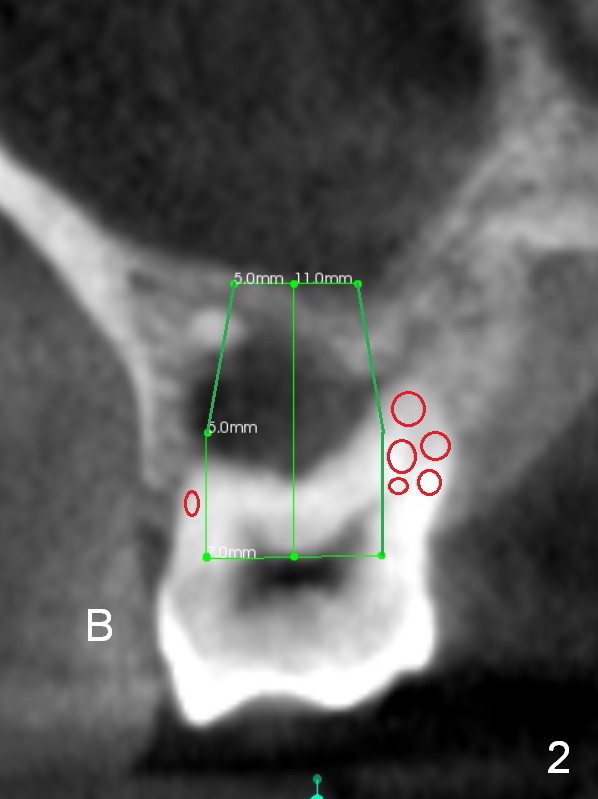

A 52-year-old lady (ZJ) has severe bone loss at #3 (Fig.1 (CT sagittal section)). After extraction, the socket will be treated with Metronidazole. A small amount of apical bone is available for primary stability; the bone density is also low (300-500 Hounsfield Units, Fig.3 (axial section)). Use RT2,3 for creating osteotomy and bone condensation, followed by 4.5-7x14 mm taps (11 mm deep; gingival margin). Prior to bone grafting (Fig.1,2 (coronal section) red circles), apply Endogain against the root surface of the neighboring teeth.